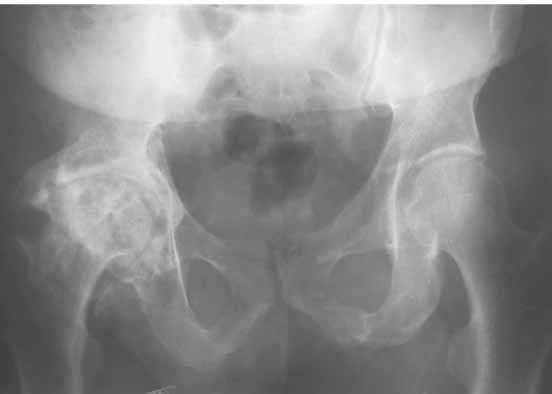

Для ответа на Ваши вопросы нужна, как минимум, обзорная

рентгенограмма таза в прямой проекции - многое станет ясно без слов.

Обзорная рентгенограмма таза просто необходима. Удивительно, почему она не сделана сразу же после установки протеза.

После ее получения можно будет продемонстрировать причины проблемы.

1. AP X ray of the Pelvis is a must. It will likely show that right hip/ femur is longer than left. Even based on Rt Hip AP X Ray it is my impression.